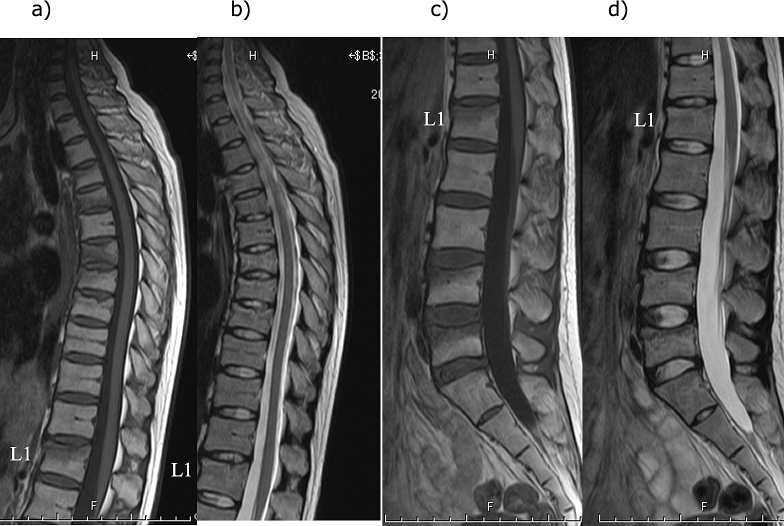

Fig. 2.

Magnetic resonance imaging findings for the thoracic and lumbar spine

a) Thoracic spine T1-weighted image, b) Thoracic spine T2-weighted image, c) Lumbar spine T1-weighted image, d) T2-weighted image. L1: First lumbar vertebra

A wedge-shaped deformity is observed in the 5th, 7th, 8th, 9th, and 10th thoracic vertebrae and the 4th and 5th lumbar vertebrae.

A simple X-ray showed multiple vertebral body deformities (Fig. 1). Magnetic resonance imaging (MRI) showed T1 low and T2 high signals in the 4th, 5th, 7th, 8th, and 9th thoracic vertebrae and the 1st, 4th, and 5th lumbar vertebrae, indicating fresh multi-vertebral fractures (Fig. 2). Bone mineral density was assessed using dual X-ray absorptiometry (DXA) (Discovery DXA System; Hologic Inc., Marlborough, MA, USA). It was 0.498 g/cm2 (49 % young adult mean [YAM]) for the lumbar spine and 0.498 g/cm2 (63 % YAM) for the hip (Table 1).